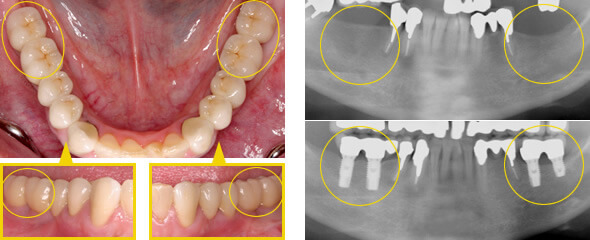

インプラントの治療例

どれがインプラント治療した

歯でしょうか?

治療①

オールセラミッククラウンを装着。天然歯と見分けが付かない色調。

治療例

期間 3ヶ月~1年 9~12回

内容 失った部位にインプラントを埋入

歯肉骨増生を行い天然歯を削らずに修復

費用(税別) ¥400,000~¥500,000

治療②

オールセラミック、ジルコニアで自然感のある状態に修復。奥歯でしっかり噛めるようになりました。

大臼歯2本をインプラントに

大臼歯2本をインプラント。小臼歯1本も同時に修復。

土台をインプラントに固定

ジルコニアの土台をインプラントに固定。

自然感のある状態に修復

期間 7回

内容 欠損にインプラントを2本埋入し修復